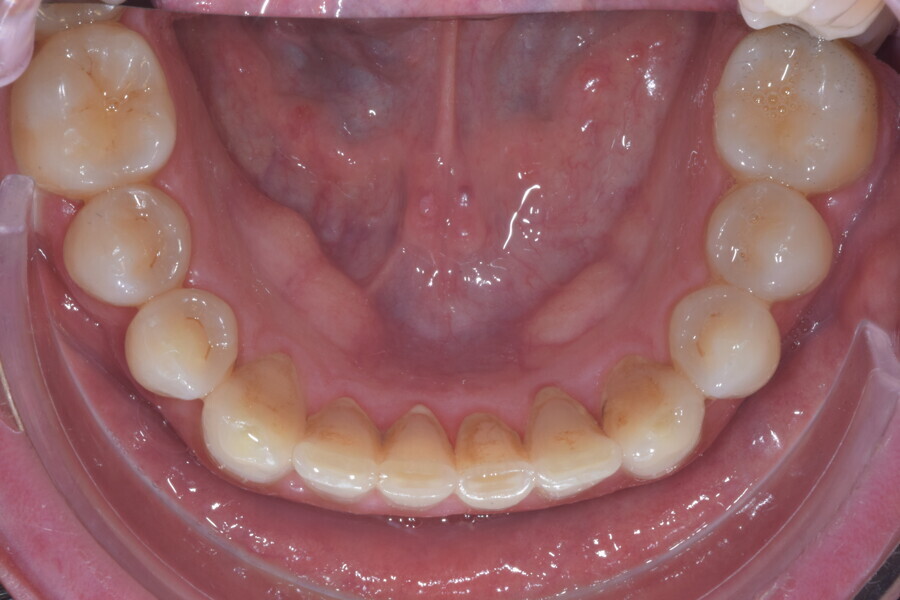

Le motif principal de consultation de ce patient âgé de 37 ans, était de rétablir l’alignement des dents antérieures sur les deux arcades. L’analyse faciale a indiqué une face courte avec un profil plat, mais une projection normale du menton (Figs. 9–12), et l’examen clinique a révélé une classe squelettique de type I (angle ANB = 0,89°) et une malocclusion de classe I avec supraclusion sévère (près de 100 %), une courbe de Spee très prononcée, un torque normal de l’incisive centrale supérieure (Ui-FH = 110°), un encombrement dentaire léger sur l’arcade maxillaire et modéré sur l’arcade mandibulaire (Figs. 13–18). Chez ce patient, les composantes de la supraclusion correspondaient à une dysmorphie squelettique grave correspondant à une hypodivergence (FMA = 14,24°), avec une inclinaison normale des incisives supérieures et inférieures et un angle goniaque réduit (110,46°). L’analyse du cliché céphalométrique indiquait une hauteur réduite de l’étage inférieur de la face associée à l’hypodivergence (Fig. 19). La seule option de traitement envisagée était un traitement orthodontique par aligneurs avec tous les éléments auxiliaires décrits (rampes d’occlusion, zones de pression, nivellement de la courbe de Spee dans les trois dimensions, élastiques de classe II et puissants contacts occlusaux) afin de corriger la supraclusion.

Le plan de traitement numérique (ClinCheck) avait prévu douze aligneurs pour l’arcade maxillaire et dix-sept pour l’arcade mandibulaire. Les objectifs du traitement visaient à combiner les mouvements verticaux d’extrusion des dents postérieures et les mouvements d’intrusion des dents antérieurs, au moyen de rampes d’occlusion, tout en utilisant des taquets d’extrusion pour assurer la désocclusion des dents postérieures et l’intrusion des dents antérieures inférieures, nécessaires au nivellement de l’arcade mandibulaire. La courbe de Spee a été nivelée et le profil plat ainsi que la position des lèvres ont été améliorés par une vestibulo-version des incisives supérieures et inférieures. Le plan avait prévu des élastiques de classe II pour faciliter la vestibulo-version des dents inférieures et les puissants contacts occlusaux postérieurs, avec une extrusion relative des dents postérieures. Une morphologie plus large de l’arcade et une intercuspidation idéale ont été obtenues par des mouvements de torque proches de 0° des dents latérales et postérieures supérieures. Aucune conception technique excessive n’avait été prévue dans le plan de traitement numérique. En raison de l’âge du patient, les aligneurs ont été changés tous les dix jours, dans le cadre d’un traitement d’une durée inférieure à six mois. À la fin de la première série d’aligneurs (Figs. 20–24), un nouveau plan de traitement numérique comportant cinq autres aligneurs a été conçu, en vue d’améliorer l’intercuspidation des molaires sans élastiques. La durée totale du traitement a donc été prolongée jusqu’à 7,5 mois puisque les aligneurs supplémentaires étaient changés toutes les semaines.